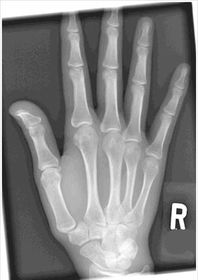

| PA Hand | distal phalynxes are bent flatten hand to true PA *should be equal concavity on all digits* |

| PA Hand | obliqued - fingers are not equally concave on both sides distal metacarpals are overlapped |

| PA Hand | ANATOMY: entire hand including 1'' of distal radius and ulna CRITERIA: equal concavity on either side of digits digits separated with no superimposition open joint spaces POSITIONING: CR perpendicular @ 3rd MCP joint |